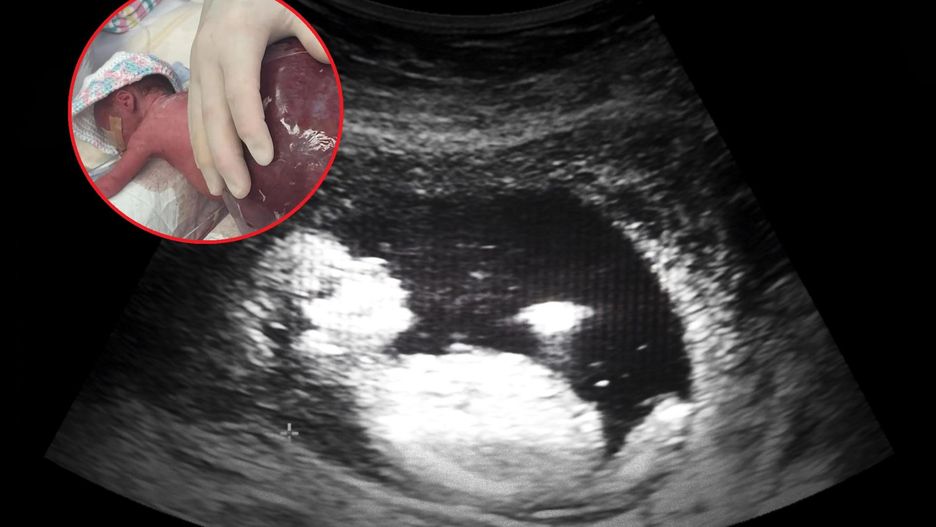

W jednym z australijskich szpitali uratowano dziewczynkę, która urodziła się z potworniakiem okolicy krzyżowo-guzicznej dwukrotnie większym od niej samej. Taka zmiana dotyka jedno na 40 tys. żywych urodzeń. To dzięki przeprowadzonym badaniom prenatalnym lekarze mieli wiedzę o stanie zdrowia dziecka i mogli podjąć działania, by mu pomóc. Zabieg usunięcia guza odbył się zaraz po porodzie i trwał sześć godzin. [image type="big" title="Dziewczynka urodziła się z guzem większym niż całe jej ciało" source="Facebook" link="" image="https://portal-abczdrowie.wpcdn.pl/2022/11/07/zdjg_41bd.jpg" width="1920" height="1080" x="" y="" x2="" y2="" croppedPath="https://portal-abczdrowie.wpcdn.pl/imageCache/2022/11/07/zdjg_41bd.-x0y0xx0yy0.jpg" ]

- Moja córeczka ważyła 1025 gramów, a guz na jej plecach dwa kilogramy - był ogromny. Zaraz po porodzie przeszła sześciogodzinną operację usunięcia potworniaka krzyżowo-guzicznego - wspomina Rachel.

Profesor Saliesh Kumar, który operował dziewczynkę, przekazał, że guz Saylor był największym, z jakim się spotkał w trakcie swojej kariery zawodowej.